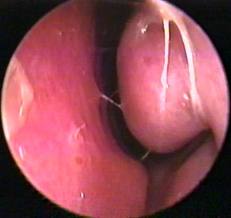

啥是鼻息肉?很多鄉民先進會誤認 下鼻甲(inferior turbinates)為鼻息肉(nasal polyp),鼻息肉 大多是發生在有 鼻竇炎 或者 嚴重過敏性鼻炎 的鼻內,它的起源是 鼻竇腔 或是 鼻咽腔的黏膜

.一開始小小的不顯眼,隨著一再的累積而增厚加大, 越長越大,情況大概如照片所示.